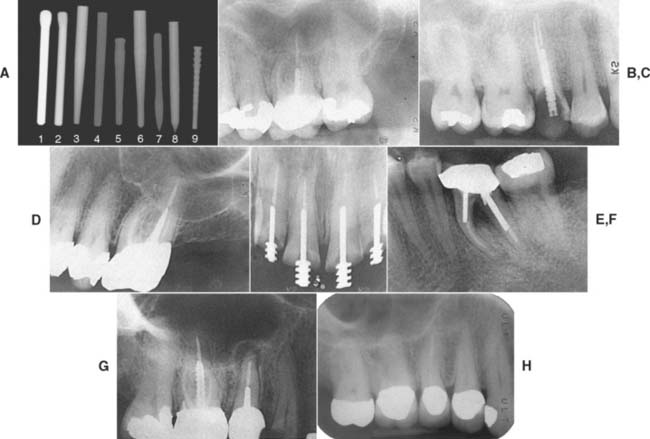

The advantages and disadvantages of different post types are summarized in Table 12-4. Because no system has universal application, being familiar with more than one technique is a significant advantage. A wide range of prefabricated posts are available. They come in many shapes and sizes and have varying radiopacity that may assist in their identification (Table 12-5 and Figs. 12-25 and 12-26).

Fig. 12-25 Classification of prefabricated posts. A, Tapered smooth posts. B, Tapered serrated posts. C, Tapered threaded posts. D, Parallel-sided smooth posts. E, Parallel-sided serrated posts. F, Parallel-sided threaded posts.

(Redrawn from Shillingburg HT, Kessler JC: Restoration of the Endodontically Treated Tooth. Chicago, Quintessence Publishing, 1982.)

Fig. 12-26 The various endodontic posts encountered in clinical practice present with varying degrees of radiopacity. Dentists accustomed to seeing traditional stainless steel and titanium posts may be deceived by more recently introduced systems. A, Nine representative posts: (1) ParaPost stainless steel (Coltène/Whaledent); (2) ParaPost titanium (Coltène/Whaledent); (3) FRC Postec Plus (Ivoclar Vivadent); (4) Glass Fiber Post (Ellman International); (5) Glass Fiber C-I Post (Parkell); (6) D. T. Light-Post (Bisco); (7) Twin Luscent Anchors (Dentatus USA); (8) Unicore (Ultradent Products); (9) PeerlessPost (SybronEndo). The pure carbon fiber posts (not included in A) are completely radiolucent. The type of cement that is used plays a role in the radiopacity of the post (see Fig. 31-6). B to I, Radiographs of the six categories: B, Endowel (Star Dental), tapered and smooth sided. C, Unimetric (DENTSPLY), tapered and serrated. D, Surtex (Dentatus USA), tapered and threaded. E, CTH Beta Post (CTH), parallel-sided and smooth. F, ParaPost (Coltène/Whaledent) (two sizes), parallel-sided and serrated. G, Flexi-Post (Essential Dental Systems) (in the right maxillary first molar), parallel-sided and threaded (note the split shank). H, ParaPost Fiber Lux (Coltène/Whaledent) cemented with RelyX Luting (3M ESPE). Note the radiolucency of the post in comparison with the radiopacity of the gutta-percha endodontic fill.

(B, Courtesy of Dr. D. A. Miller and Dr. H. W. Zuckerman; C, courtesy of Dr. I. A. Roseman; D, courtesy of Dr. F. S. Weine and Dr. S. Strauss; E, courtesy of Dr. J. F. Tardera; F, courtesy of Dr. J. L. Wingo; G, courtesy of Dr. L. R. Farsakian; H, courtesy of Dr. D. A. Miller and Dr. G. Freebeck.)